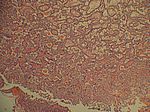

Nebenschilddrüsen-Hyperplasie, HE